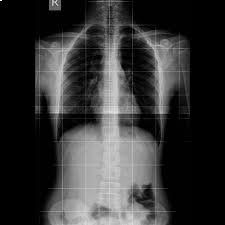

La radiologia convenzionale è l’esame di primo livello per lo studio di molteplici distretti corporei e in particolare dell'apparato respiratorio e scheletrico (cranio, colonna vertebrale, segmenti ossei). Questa metodologia fornisce importanti indicazioni di base su molte patologie, sia traumatiche che degenerative e artrosiche nonché malformative. La radiologia convenzionale si risulta anche di grande efficacia per individuare patologie o problematiche all'apparato urinario e all'addome, da approfondire successivamente con esami diagnostici più accurati e precisi.